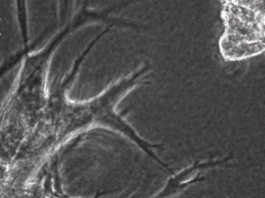

Xem ung thư biến tế bào khỏe mạnh trở thành “tay sai đắc lực”